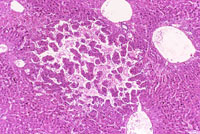

A hemangioma has destroyed the normal hepatic parenchyma. A thrombus is present at the top of the hemangioma; high magnification shows dilated vascular channels lined by flattened endothelial cells. There is minimal atrophy of hepatic cords.